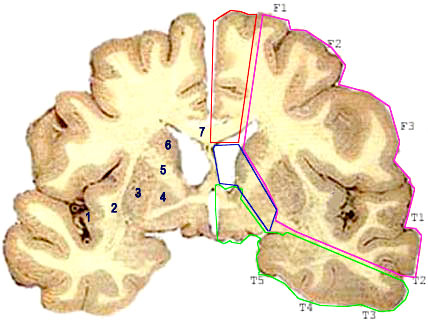

Coupe frontale (Charcot)

Territoires vasculaires

-1: cortex insulaire

-2: avant-mur

-3: putamen

-4: globus pallidus

-5:capsule inter (bras antrieur)

-5': bras postrieur

-6: noyau caud (tte)

-6': noyau caud (queue)

-7: corps calleux (genou)

-7': corps calleux (bourrelet ou splenium)

-8: scissure calloso-marginale

-9: scissure pricalleuse

-10: scissure calcarine

Territoires encadrs en:

- rouge: artre crbrale antrieure

- violet: artre crbrale moyenne

- en vert ; artre crbrale postrieure

- en bleu: artre chorodienne antrieure

Coupe horizontale (Fleshig)